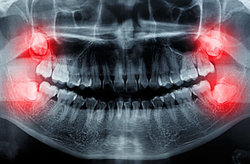

دندان عقل همیشه کشیدنی نیست

یک متخصص جراحی لثه و ایمپلنت گفت: دندان عقل همیشه کشیدنی نیست و حتی نگهداری آن مفید است.

وی با اشاره به اینکه همواره وجود دندان عقل به معنای کشیده شدن آن نیست و در بسیاری از موارد به لحاظ شرایط و موقعیت دندان عقل در جویدن به دندان‌های آسیاب کمک می‌کند، افزود: در صورتی که رویش دندان عقل مناسب بوده و آسیبی به لثه اطراف وارد نکرده باشد، وجود آن مشکلی ندارد. اما به دلیل اینکه بیشتر از سایر دندان‌ها دچار ناهنجاری می‌شود، اغلب یا به ترمیم ریشه آن پرداخته می‌شود و یا گفته می‌شود بهتر است که کشیده شود.

این جراح لثه و ایمپلنت با بیان اینکه گاهی به دلیل کج بودن رویش دندان نیز لازم است این دندان کشیده شود، افزود: زیرا چرخش کاملی در آن صورت نمی‌گیرد و دندان کج می‌ماند و البته در این حالت کشیده شدن آن لازم است. تنها در صورتی که وجود دندان منجر به ناهنجاری‌ها شود، توصیه به کشیده شدن یا جراحی آن می‌شود.

منصوری تصریح کرد: به صورت کلی تمیز کردن مرتب دندان عقل به منظور جلوگیری از پوسیدگی، بیش از دندان‌های جلویی لازم است؛ زیرا در غیر این صورت علاوه بر التهاب لثه اطراف دندان، در برخی موارد منجر به ایجاد کیست نیز می‌شود و حالت بد خیمی پیدا می‌کند.

وی گفت: در برخی موارد نیز به منظور ارتودنسی و مرتب کردن دندان‌ها، دندان عقل کشیده می‌شود. البته در صورتی که تشخیص داده شود که لازم است دندان عقل کشیده شود، بهترین سن کمتر از ۳۵ سال است؛ زیرا عوارض جراحی و کشیده شدن کمتر و ترمیم آن بهتر انجام می‌شود.

وی تصریح کرد: البته مجددا تاکید می‌کنم که دندان عقل همیشه کشیدنی نیست و حتی نگهداری آن مفید است. برای نمونه در بسیاری از جراحی‌ها می‌توان از استخوان این ناحیه استفاده کرد و یا حفظ دندان عقل در حفظ ارتفاع صورت زمانی که دندان‌های جلویی کشیده می‌شوند، موثر است.

منصوری اضافه کرد: در بسیاری از موارد دندان عقل دندان مفیدی برای شخص محسوب می‌شود و باید دندانپزشک تشخیص کشیده شدن آن را بدهد؛ زیرا در بسیاری از مواقع قابل ترمیم و درمان است. دندان عقل هیچ فرقی با دندان‌های دیگر به لحاظ ساختاری ندارد.